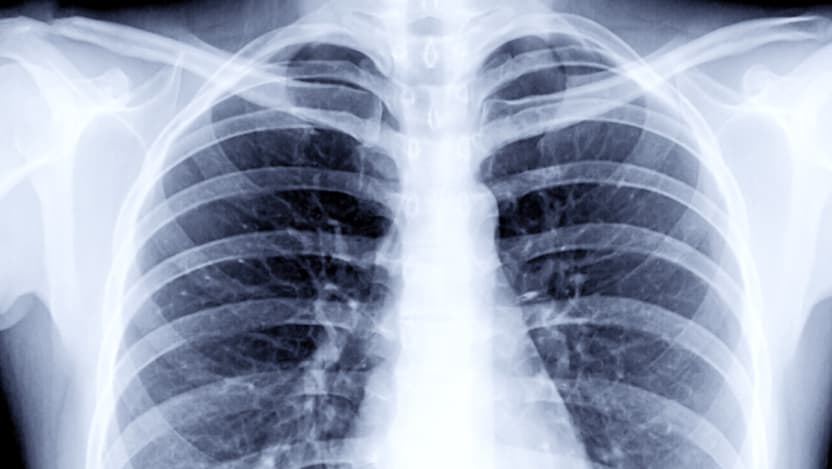

Medical images provide important windows into the detection, diagnosis and monitoring of diseases like COVID-19; for example, X-rays or CT scans of the lungs have the potential to help doctors determine the severity of the disease and decide on an optimal treatment course for a patient. But examining individual images is time consuming and difficult for physicians, and automated systems can improve accuracy and speed. For artificial intelligence (AI) to accurately analyze any given scan, many thousands of images first must be collected and annotated to train machine-learning algorithms.